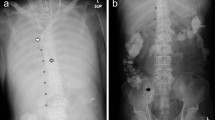

To identify a suitable anatomical model for the site of connection, imaging data of patients in supine position were analyzed and evaluated. A board-certified radiologist selected CT data of 24 patients with healthy vascular systems. All imaging data were anonymized. Three data sets were excluded due to insufficient image quality, two data sets due to abnormal anatomy of the venous vessels, and one data set due to an extreme deformation of the spine. We segmented and measured the remaining 18 data sets at distinctive locations (Fig. 1). Therein, D1 is the diameter of the IVC, measured at the level of the first lumbar vertebra and D2, also the diameter of the IVC, but measured just after the convergence of the CIVs to the IVC. D3, D4, D5, and D6 are diameters of the CIVs: D3 (right branch) and D4 (left) are measured just before the convergence into the IVC whereas D5 (right) and D6 (left) are measured just after the convergence of the external and internal iliac vein into the CIVs. D7, D8, D9, and D10 are diameters of the external iliac vein, whereby D7 (right) and D8 (left) are measured just before the convergence of the external and internal iliac vein into the CIVs and D9 (right) and D10 (left) are measured just after the transition from the femoral vein to the external iliac vein. Additionally, we measured the distances between D1 and D2, D3 and D5 (length of right CIV), and D4 and D6 (length of left CIV). Furthermore, the angles between IVC and each CIV as well as the angle between both CIVs were measured. The segmentation and measurement of the diameters and distances were performed using Mimics Research 20.0 (Materialise NV, Leuven, Belgium). For the measurement of the angles, we exported the centerline into Creo Parametric 4.0 (PTC Inc., Boston, MA).

The results of the anatomical analysis of the 18 image data sets are presented in Fig. 5. The mean diameter ± standard deviation of the IVC at the level of the first lumbar vertebra is 25.8 ± 3.3 mm and decreases on a mean length of 138.4 ± 17.8 mm towards the CIVs to a mean diameter of 22.9 ± 2.7 mm. Just before the convergence of the CIVs to the IVC, the right and the left CIV have a mean diameter of 15.9 mm with a standard deviation of 2.8 mm and 3.3 mm, respectively. The right CIV is on average 63.6 ± 18.0 mm long, whereas the left CIV is longer, with an average length of 81.4 ± 14.8 mm. The right and left vena iliaca externa show similar diameters just before the convergence into each CIV, 14.4 ± 2.4 mm and 14.3 ± 2.9 mm, respectively. The same applies for the diameters at the beginning of both right and left vena iliaca externa, as they show a diameter of 13.3 ± 2.6 mm and 13.1 ± 2.4 mm, respectively. The angles between the IVC and each CIV show the highest variances: The angle between IVC and right and left CIV are 142.0 ± 37.1° and 135.7 ± 37.4°, respectively. The angle between both CIVs shows a lower variance, with 83.3 ± 6.1°.

Boxplots of the anatomical measurements, wherein the value of the selected anatomy are marked with a red “X”: (a) Diameter D1, (b) Diameter D2, (c) Distance D1-D2, (d) Diameter D3 & D4, (e) Diameter D5 & D6, (f) Distances D3-D5 & D4-D6, (g) Angle G-L & G-R (h) Diameter D7 & D8, (i) Diameter D9 & D10.

The performed analysis entailed two candidate anatomies for the subsequent CFD simulations: subject 3 and 10. Because of the limited field of view of subject 10, a measurement of D1 was not possible and therefore, we selected the anatomy of subject 3. The respective measurements of subject 3 are marked in Fig. 5.